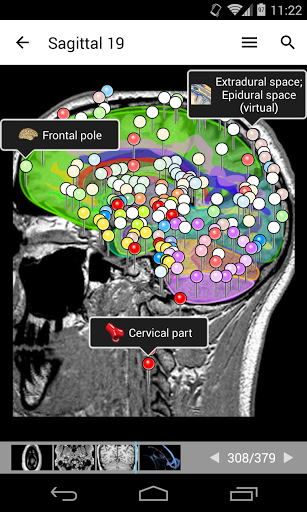

-The pins mode have a new behaviour allowing you to follow an anatomical structure much more easily

-Within the details view of an anatomical structure, a pin now points the related structure in all present images

Also tap directly on the image to navigate to the presented image in that module